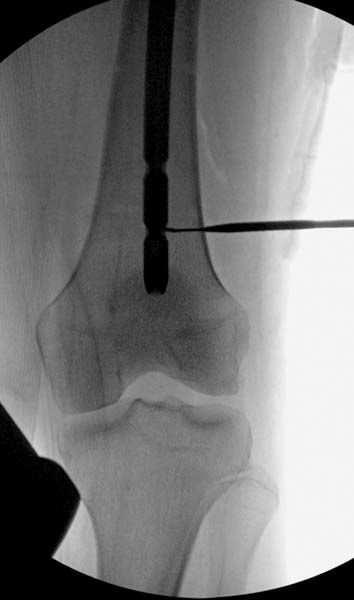

Закрытый БИОС решает множественные проблемы связанные с лечением переломов, но проблема дистальной блокировки без рентгена до сих пор остается нерешенной. Рекламированные производителями приспособления для дистальной блокировки из-за различной кривизны кости не эффективны или стоит очень дорого (Smith&Nephew SureLock). Задержка операции из-за блокировки не всегда удовлетворяет, и многих вынуждает искать альтернативные методы фиксации. С результатами таких действий, остеомиелитом и несращениями, встречаемся в ежедневной жизни..

Для решения проблемы дистальной блокировки компания DigiMed недавно предложила систему блокировки без рентгена. Пока в стране только два набора и только для антеградных гвоздей, но компания работает над созданием устроиства для других гвоздей тоже..

Результат первых случаев показала отсутствие разницы между занятиями на муляжах, а также Workshop и с удивительной точностью вывел латерально над кожей специальное сверло. Дальше по сверлу тонкий направитель и проводится сверление каннюлированным сверлом....